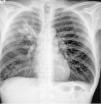

Neumonía por Rhodococcus equi en un paciente con infección por el VIH. A propósito de un caso

Rhodococcus equi neumonia in a HIV infected patient: a case report